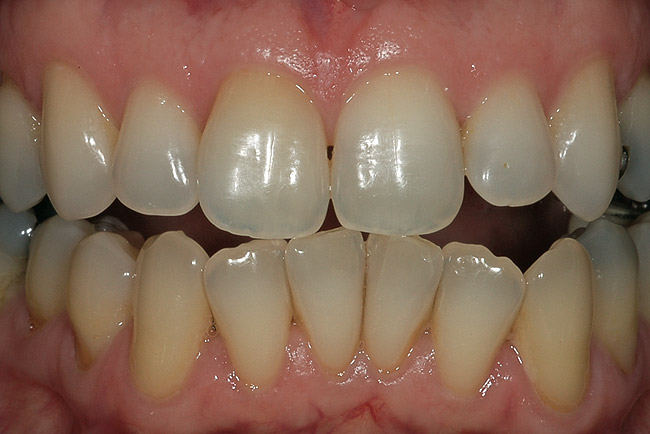

Figure 1  A clinical examination demonstrates a single, very dark lateral incisor and a moderately dark central incisor with a crown on the adjacent central incisor and several dark gingival areas.

Figure 1

Figure 6  A single dark tooth from trauma needs to be examined carefully and evaluated with a radiograph. The safest approach is to bleach this tooth alone until the toothís response and maximum lightening can be determined.

Figure 6

Figure 9  A reasonable match was obtained from about 8 weeks of single-tooth bleaching. Often patients discontinue treatment when the single tooth is no longer a mismatch, even if the outcome is not ideal.

Figure 9